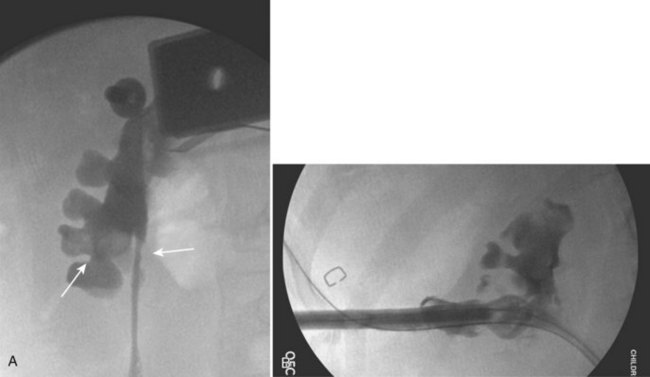

The decision to use a flexible (6.9-Fr) or semirigid (7.5-Fr) ureteroscope is determined on size and location of stone, anatomic factors, and individual surgeon preference. Rigid or semirigid ureteroscopy for ureteral calculi is routinely performed with a safety wire in place, while flexible ureteroscopy is performed with both a safety and working wire in place. Ureteral access sheaths (internal diameter of 9.5 Fr) are routinely used to facilitate flexible ureteroscopy, especially in cases of large proximal ureteral stones and heavy renal pelvis stone burdens. Access sheaths may also serve to facilitate flexible ureteroscopy when altered anatomy or torturous ureters are encountered (Fig. 135–5).

Figure 135–5 Altered anatomy in a 17-year-old male spina bifida patient who underwent a high thoracic myelomeningocele closure at birth (A). A computed tomography (CT) scan performed for a gross hematuria workup revealed bilateral nephrolithiasis in pelvic kidneys (B). The right retrograde pyelogram (C) demonstrated the lower pole stone (short arrow) and a torturous ureter almost taking a perpendicular course (long arrow). Placement of a ureteral access sheath (D) straightened the ureter (white arrow). This allowed easier access to address the stone (short arrow in D) with a flexible ureteroscope (E).